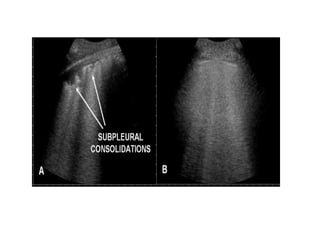

Tissue pattern representative of Alveolar

Consolidation

Presence of hyperechoic punctiform

images

imagesrepresentative of air bronchogramsrepresentative of air bronchograms

Pleural

effusion

Tissue pattern representativeof Alveolar Consolidation Presence of hyperechoic punctiform images Presence of hyperechoic punctiform imagesrepresentative of air bronchogramsrepresentative of air bronchograms Pleural effusion Lower lobe